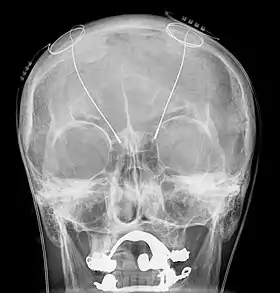

DBS-probes shown in X-ray of the skull (white areas around maxilla and mandible represent metal dentures and are unrelated to DBS devices)

Deep brain stimulation (DBS) is a surgical procedure that implants a neurostimulator and electrodes which sends electrical impulses to specified targets in the brain responsible for movement control. The treatment is designed for a range of movement disorders such as Parkinson's disease, essential tremor, and dystonia, as well as for certain neuropsychiatric conditions like obsessive-compulsive disorder (OCD) and epilepsy.[1] The exact mechanisms of DBS are complex and not entirely clear, but it is known to modify brain activity in a structured way.[2]